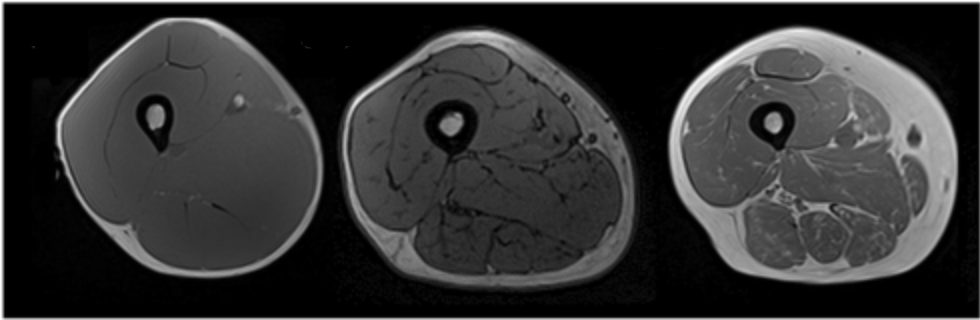

25 лет/ 35 лет/ 45 лет

Возрастная потеря мышечной массы часто сопровождается увеличением общего ожирения и отложением жира в скелетных мышцах. Этот процесс усугубляется нарушениями метаболизма, накоплением висцерального жира и воспалением, вызванным жировой тканью.